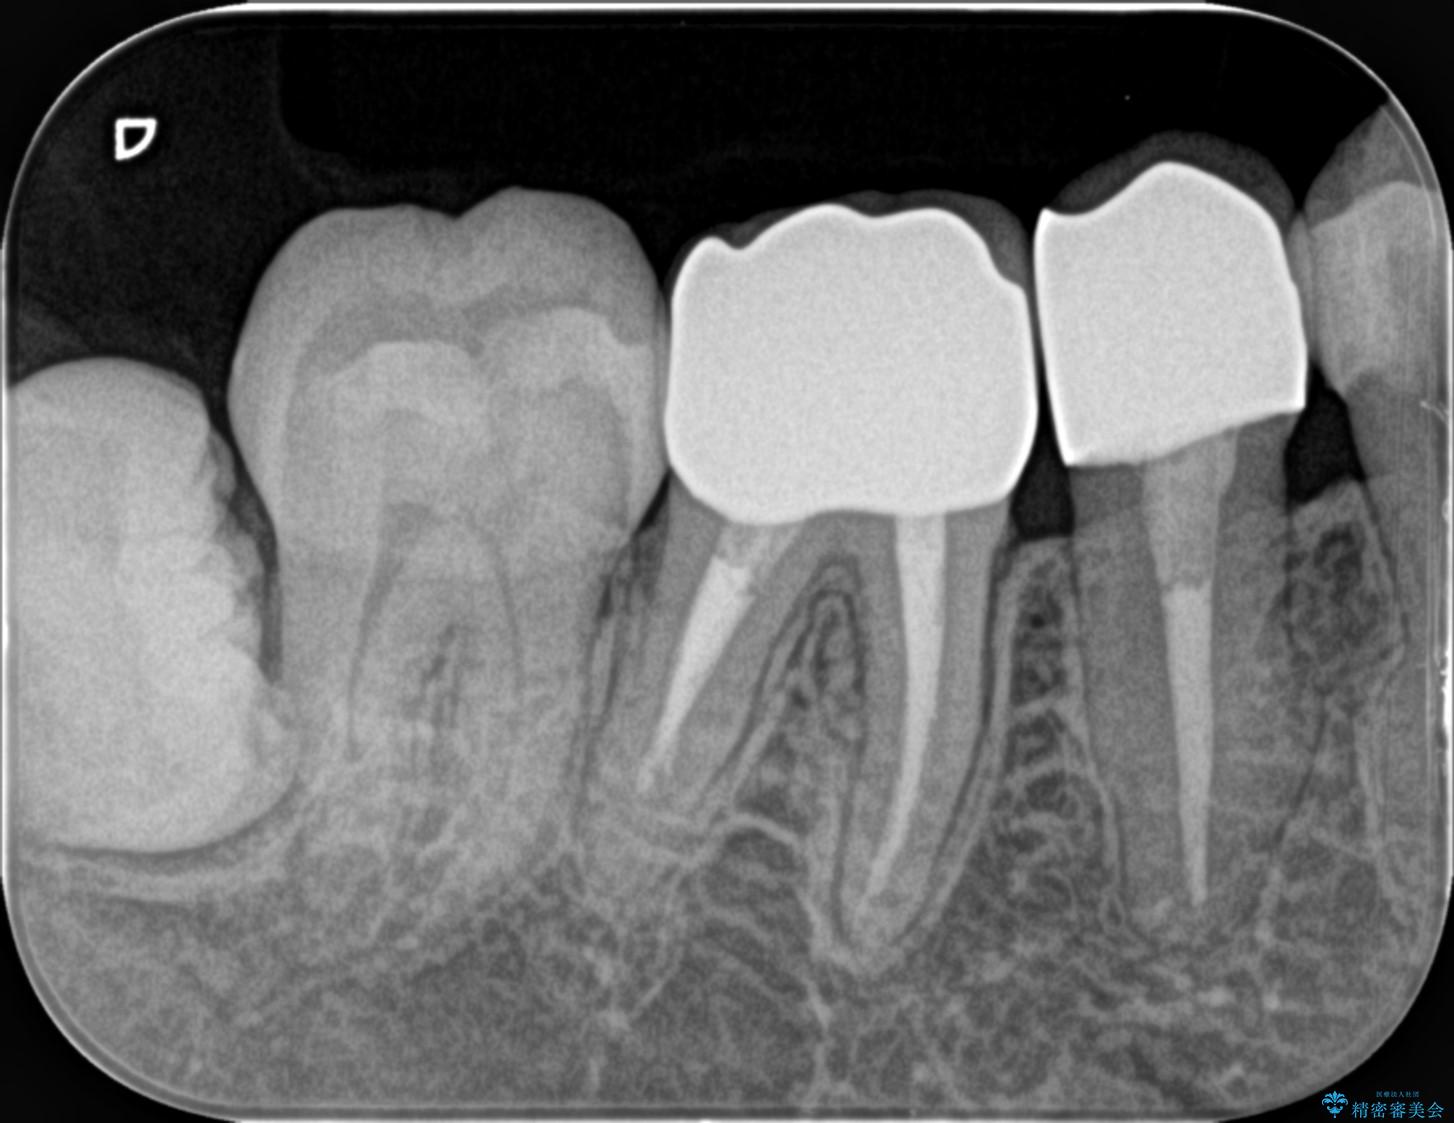

装着されていた清掃性の悪い銀歯を外すと、銀歯の下で歯ぐきよりも深い虫歯が再発していました。

虫歯を丁寧に除去し、歯周外科を用いて周囲の歯ぐきの炎症を除去します。その後、清掃性の高い精密なセラミック治療をおこなっていきます。